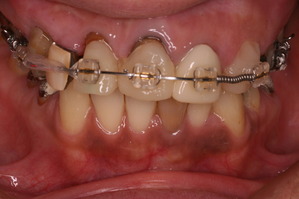

前歯の根っこの治療を終了して仮歯を入れたところです。

上からみると向かって左側のみダミーの部分があり、かり歯を入れた右側は仮歯の大きさで隙間をふさいでます。

上下の真ん中の線も不一致ですので、矯正治療で可能な限り顔面の真ん中と歯の真ん中が一致するように努力します。